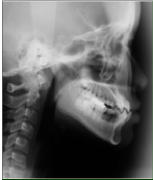

- レントゲンとセファロ分析

_